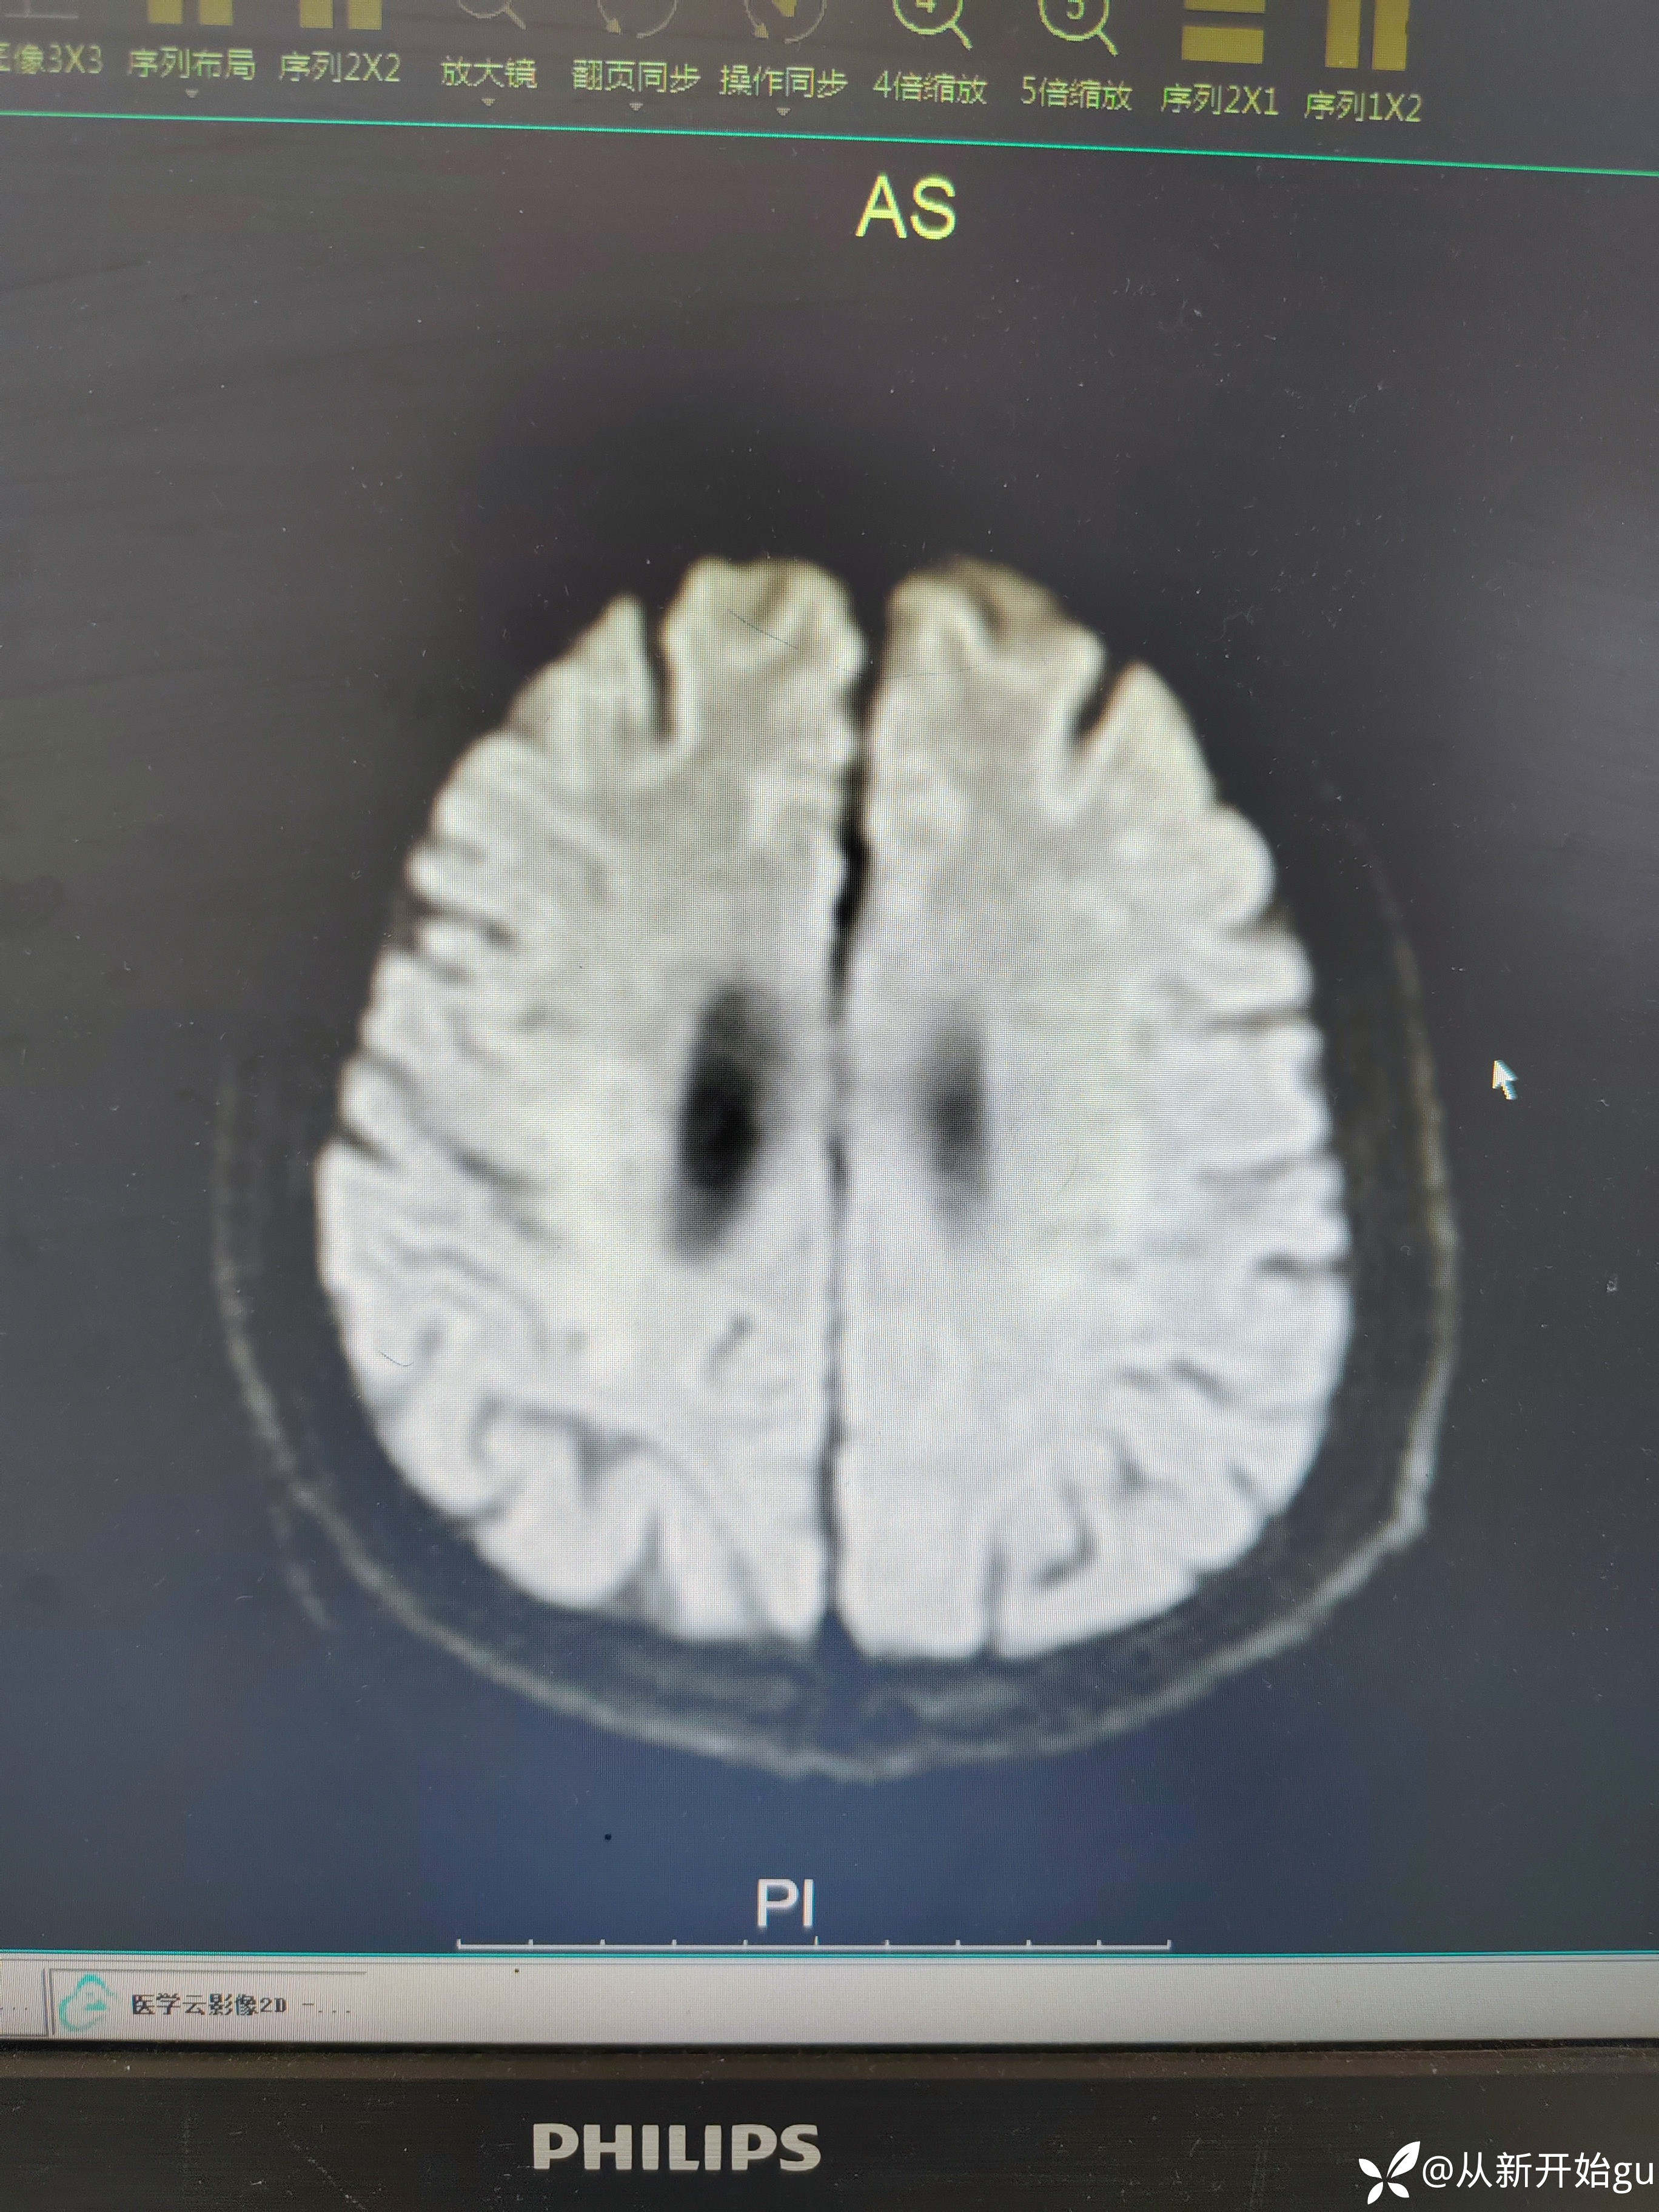

患者男性53岁,主因被发现左下肢活动障碍2.5小时来院,(患者下夜班,于上午9点休息,下午3点醒后出现症状)。既往脑梗死病史9个月,遗留言语不利及口角歪斜的症状。查体:右侧鼻唇沟稍浅,神舌右偏,左侧下肢肌力4级,左侧指鼻试验欠稳准,左侧巴氏征阳性。外院完善颅脑CT无出血改变。来院后完善核磁检查如图所示。